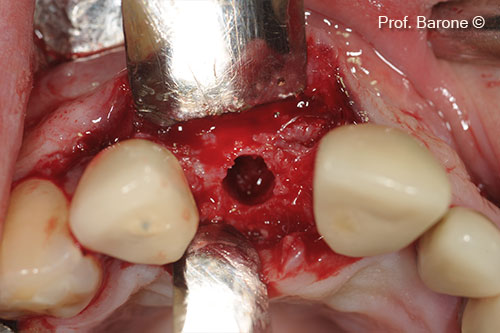

Implant site preparation

Implant inserted in the augmented ridge